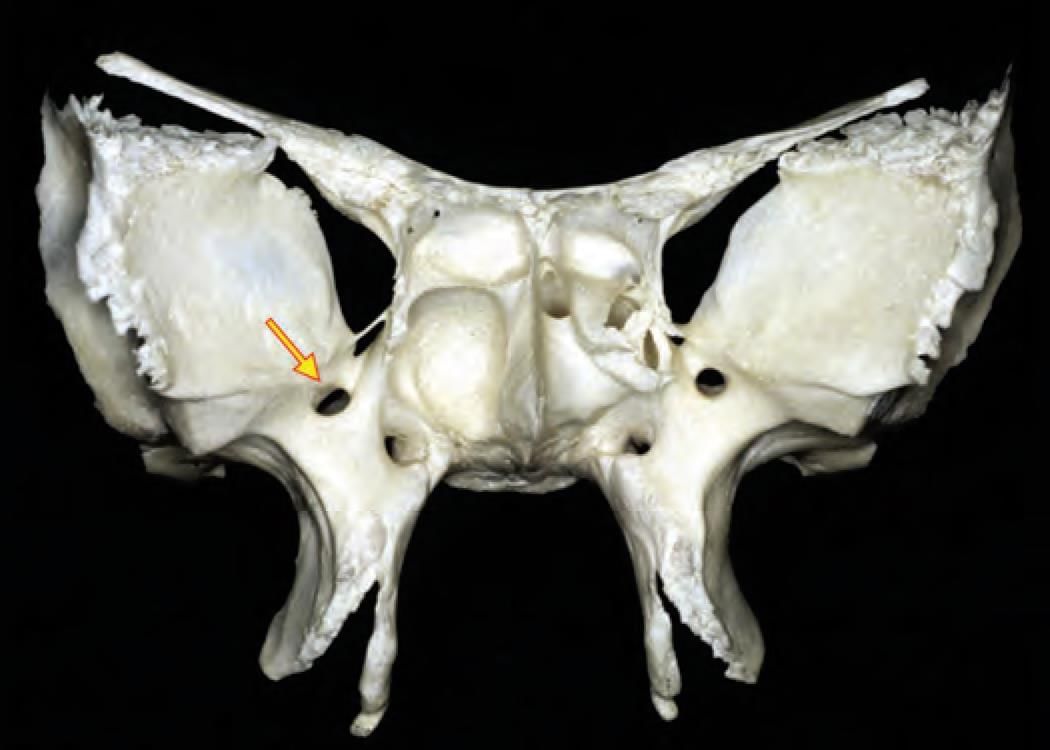

The arrow marked foramen is: (INI-CET Nov 2020)

Detailed Solution for Test: Anatomy - 3 - Question 16

The bone shown in the illustration is a frontal (anterior) view of the sphenoid bone, with a marker positioned at the foramen rotundum. The maxillary nerve travels through the foramen rotundum anteriorly to access the pterygopalatine fossa. Note that there is another opening visible infero-medial to the marker, which is the Vidian (pterygoid) canal. The Vidian nerve from the pterygoid canal carries the combined axons of the greater petrosal nerve and the deep petrosal nerve. These axons, formed at the foramen lacerum, proceed anteriorly through the Vidian canal to reach the pterygopalatine fossa.

The sphenoid bone is characterised by its butterfly-like shape, comprising:

• A central body, which contains pneumatic sphenoid air sinuses.

• Two lesser wings, which are relatively smaller and extend supero-laterally from the body.

• Two greater wings, which are comparatively larger and extend laterally from the body.

• Two legs (pterygoid processes) with pterygoid plates that project inferiorly from the body.

The superior orbital fissure is located between the lesser wings (superiorly) and the greater wings (infero-laterally). A neurovascular bundle passes through this fissure, including cranial nerves III, IV, VI, and branches of the ophthalmic nerve (a division of the trigeminal nerve). The pterygoid muscles (medial and lateral) originate from the lateral pterygoid plate.